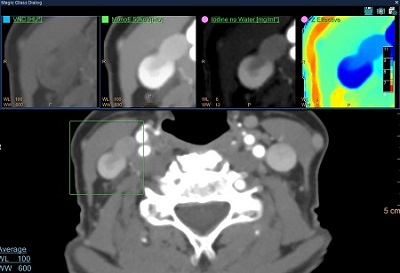

CT Spectral

Summary

Assist clinicians in viewing and evaluating CT Angiography (CTA) cases, as contrast enhanced and whole-body CTA scans, acquired on the IQon CT scanner for the inspection of contrast-enhanced vessels.